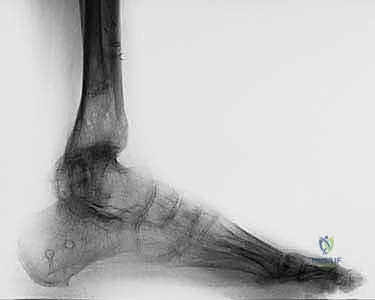

TECH FIG 2B: Lateral radiographic view showing posterior opening wedge of regenerate bone formation and posterior translation of the foot during distraction treatment with the Taylor spatial frame.